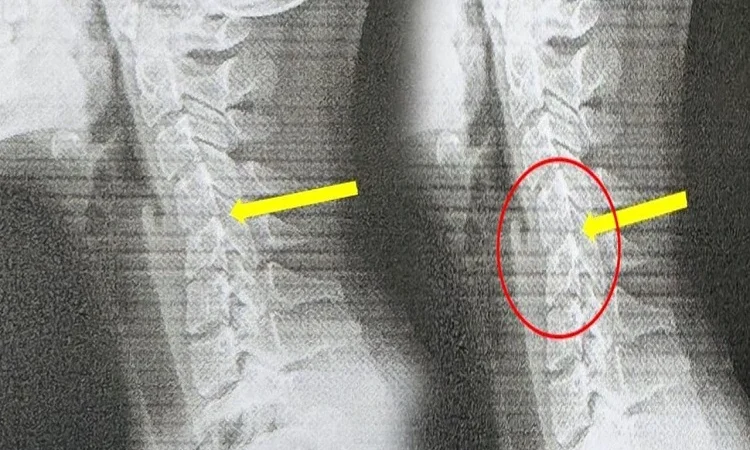

ಅತಿಯಾದ ಫೋನ್ ಬಳಕೆಯಿಂದಾಗಿ 20 ವರ್ಷದ ಯುವತಿಯ ಕುತ್ತಿಗೆ 60 ವರ್ಷದ ಮಹಿಳೆಯ ಕುತ್ತಿಗೆಯಂತೆ ಬಾಗಿದ್ದು, ಅವಳನ್ನು ಪರೀಕ್ಷಿಸಿದ ವೈದ್ಯರು. ಇದು ಅತಿಯಾದ ಫೋನ್ ಬಳಕೆಯಿಂದಾಗಿ ಎಂದು ತೀರ್ಮಾನಿಸಿದ್ದಾರೆ.

ಜೊತೆಗೆ ಅವಳ ಕುತ್ತಿಗೆ ಬಾಗುತ್ತಿತ್ತು. ವೈದ್ಯರು ತುರ್ತಾಗಿ ಸಿಟಿ ಸ್ಕ್ಯಾನ್ ಮಾಡಿದಾಗ. ಅದು ಆಘಾತಕಾರಿ ಸಂಗತಿಯನ್ನು ಬಹಿರಂಗಪಡಿಸಿತು. ಅವಳ ಗರ್ಭಕಂಠದ ಬೆನ್ನುಮೂಳೆಯು ತನ್ನ ನೈಸರ್ಗಿಕ ಆಕಾರವನ್ನು ಕಳೆದುಕೊಂಡಿತ್ತು. ಮತ್ತು ಕೆಲವು ಪ್ರದೇಶಗಳಲ್ಲಿ ಕಶೇರುಖಂಡಗಳು ಜಾರಿಬೀಳುವ ಲಕ್ಷಣಗಳನ್ನು ಸಹ ವೈದ್ಯರು ಕಂಡುಕೊಂಡರು.

‘ಟೆಕ್ಸ್ಟ್ ನೆಕ್’ ಎಂದು ಕರೆಯಲ್ಪಡುವ ಅವಳ ಸ್ಥಿತಿಯು ಅಕಾಲಿಕ ಗರ್ಭಕಂಠದ ಕ್ಷೀಣತೆಯ ಮುಂಚಿನ ಎಚ್ಚರಿಕೆ ಸಂಕೇತವಾಗಿದೆ ಎಂದು ಅವರು ಹೇಳಿದರು. ಇದರ ಬಗ್ಗೆ ಮಾತನಾಡುತ್ತಾ, ತೈವಾನೀಸ್ ವೈದ್ಯರು ಅವಳ ಸ್ಥಿತಿ. ಇಂದಿನ ಯುವಜನತೆ ಎದುರಿಸುತ್ತಿರುವ ಸಮಸ್ಯೆಯಾಗಿದೆ. ‘ಅವರು ಪ್ರತಿದಿನ ಗಂಟೆಗಟ್ಟಲೆ ತಮ್ಮ ಫೋನ್‌ಗಳನ್ನು ನೋಡುತ್ತಾ, ಕಾರ್ಯಕ್ರಮಗಳನ್ನು ನೋಡುತ್ತಾ ಮತ್ತು ಆಟಗಳನ್ನು ಆಡುತ್ತಾ ಕಳೆಯುತ್ತಾರೆ. ಆದರೆ ಅವರ ದೇಹವು ನೋವಿನಿಂದ ಕಿರುಚುವವರೆಗೂ, ಅವರಿಗೆ ಸಮಸ್ಯೆಯ ತೀವ್ರತೆಯ ಅರಿವಿರಲಿಲ್ಲ.’ ಅವರು ಹೇಳಿದರು.

ಕುತ್ತಿಗೆಯನ್ನು 60 ಡಿಗ್ರಿಗಳಷ್ಟು ಬಗ್ಗಿಸುವ ಸಾಮಾನ್ಯ ಸ್ಮಾರ್ಟ್‌ಫೋನ್ ಭಂಗಿ. ಇದು ಗರ್ಭಕಂಠದ ಬೆನ್ನುಮೂಳೆಯ ಮೇಲೆ ಸುಮಾರು 27 ಕೆಜಿ ಹೊರೆ ಹಾಕುತ್ತದೆ ಎಂದು ಡಾ. ಯೆ ವಿವರಿಸಿದರು. ಇದು ಭಾರವಾದ ಬೌಲಿಂಗ್ ಚೆಂಡನ್ನು ಅಥವಾ ಎಂಟು ವರ್ಷದ ಮಗುವನ್ನು ನಿಮ್ಮ ಕುತ್ತಿಗೆಯ ಮೇಲೆ ಹೆಚ್ಚು ಹೊತ್ತು ನೇತುಹಾಕಿದಂತೆ. ‘ಕಾಲಾನಂತರದಲ್ಲಿ, ಕುತ್ತಿಗೆಯ ಸ್ನಾಯುಗಳು ಮತ್ತು ಅಸ್ಥಿರಜ್ಜುಗಳು ಅದನ್ನು ನಿಭಾಯಿಸಲು ಸಾಧ್ಯವಿಲ್ಲ. ಡಿಸ್ಕ್‌ಗಳು ಕ್ರಮೇಣ ಕುಗ್ಗುತ್ತವೆ. ಸಂಪೂರ್ಣ ಗರ್ಭಕಂಠದ ರಚನೆಯು ಅದರ ಆಕಾರವನ್ನು ಕಳೆದುಕೊಳ್ಳುತ್ತದೆ.’